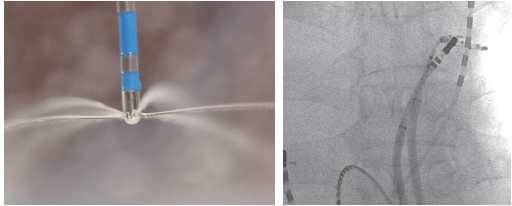

Triguy™ Irrigated Ablation Catheter představuje špičku v technologii radiofrekvenční (RF) ablace. Díky rovnoměrnému irigačnímu průtoku, ergonomickému designu a výjimečné manévrovatelnosti umožňuje vytváření hlubších, efektivnějších lézí s minimalizací rizika trombózy a charu, což zajišťuje bezpečnější a úspěšnější procedury.

Triguy™ Irrigated Ablation Catheter od APT Medical je pokročilý radiofrekvenční (RF) ablační katétr, který představuje evoluční krok v léčbě srdečních arytmií. Jeho inovativní design s řízenou irigací umožňuje lékařům dosáhnout hlubších, efektivnějších a bezpečnějších lézí, což je klíčové pro dlouhodobý úspěch ablačních procedur.

Katétr je vybaven šesti irigačními otvory, strategicky umístěnými tak, aby zajišťovaly rovnoměrné pokrytí a chlazení celého povrchu hrotové elektrody. Tato efektivní irigace minimalizuje riziko srážení krve (trombózy) na hrotu a tvorby charu, což zvyšuje bezpečnost a umožňuje kontinuální aplikaci energie.

Díky aktivnímu chlazení hrotu irigací je možné aplikovat vyšší dávky radiofrekvenční energie bez nebezpečí přehřátí povrchu tkáně. To vede k vytvoření větších, hlubších a transmurálních lézí, které jsou klíčové pro účinnou izolaci arytmogenních ložisek a dlouhodobý úspěch ablace.

Katétr nabízí rozsah vychýlení až 270°, což umožňuje spolehlivou manévrovatelnost a dosažení i těch nejsložitějších a anatomicky náročných oblastí v srdci.